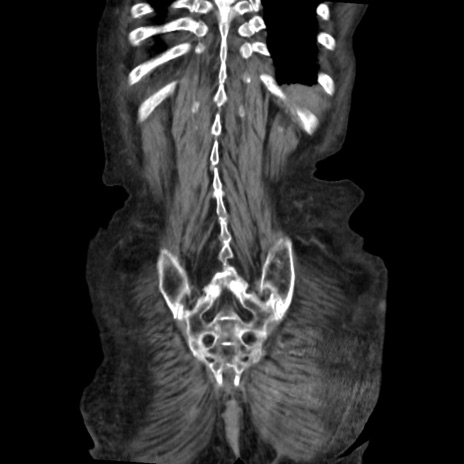

矢状断像

【症例】80歳代 女性

【主訴】腹部膨満感

【現病歴】他院にて肝硬変にてフォロー中。1週間前から便秘、腹部膨満感、臍部腫瘤あり受診となる。

【既往歴】肝硬変

【身体所見】腹部膨隆あり、皮膚変化なし、疼痛なし。

【データ】WBC 4600、CRP 0.25